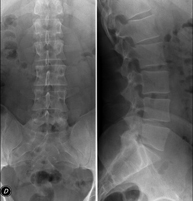

- Lumbar spine X-ray

This technique uses X-ray rendered imaging to examine the lumbar spine. Indicated for: sciatica, trauma, lower back pain.

- Spinal teleradiology

This technique uses X-ray rendered imaging to examine the entire spinal column, especially assessing the presence of scoliosis and pelvic dysmetria.

Tècnica que usa els raigs X a través de la qual s'obtenen imatges de l'abdomen (estómac, intestí prim, intestí gros, fetge, ronyons, bufeta, pelvis òssia, etc.) per al seu estudi. - RX Columna lumbar

Tècnica que usa els raigs X a través de la qual s'obtenen imatges de la columna lumbar per al seu estudi. - TEGD (trànsit esòfag-gastro-duodenal)